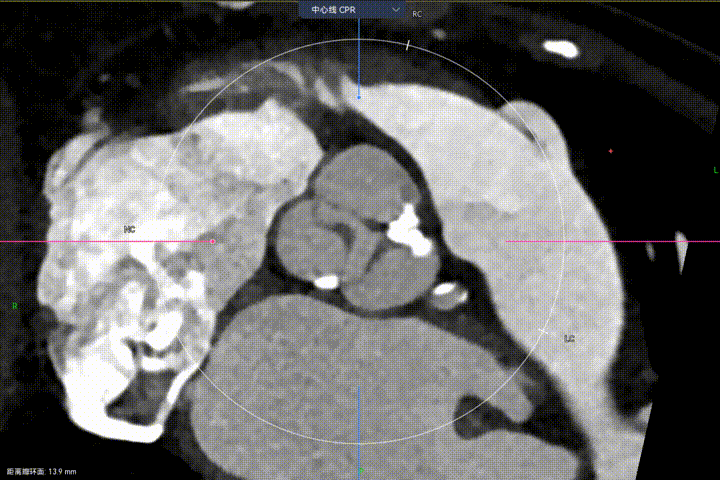

主动脉瓣环周长径21.9mm,小瓣环,LVOT直筒型结构;三叶瓣,左右融合(功能型二叶瓣),瓣叶轻微增厚并重度钙化,钙化主要分布在无冠窦瓣叶边缘及左右交界融合处,瓣上限制较重。

窦部空间适中,STJ内径偏小,升主动脉内径可。

Step 3.球囊预扩:18mm球囊预扩张,无腰无漏

Step 6.工作位观察:真实瓣环下方2mm,位置合适,决定释放,一次完成

Step 8.最终造影:真实瓣环下方3mm标准位,完全同轴,轻微反流,猪尾撤出后反流完全消失

Step 10.验证器械同轴性,完全同轴